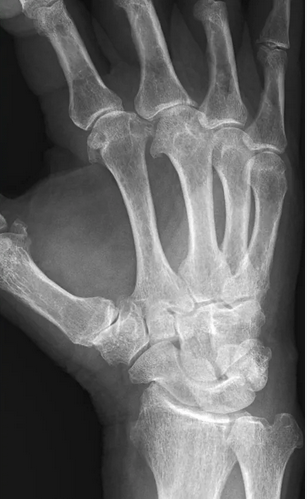

The genetic condition that most commonly causes these findings.

What is Hemochromatosis.

The condition that causes this finding:

Reticular, lacy pattern of destruction.

What is sarcoidosis (or sarcoid arthropathy).